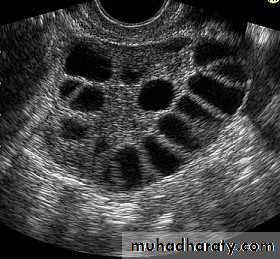

Imaging studies

*Ultrasound:Determine the presence, state and size

of ovaries and any follicular activity.Determine the presence and size of

uterusChromosomal analysis: